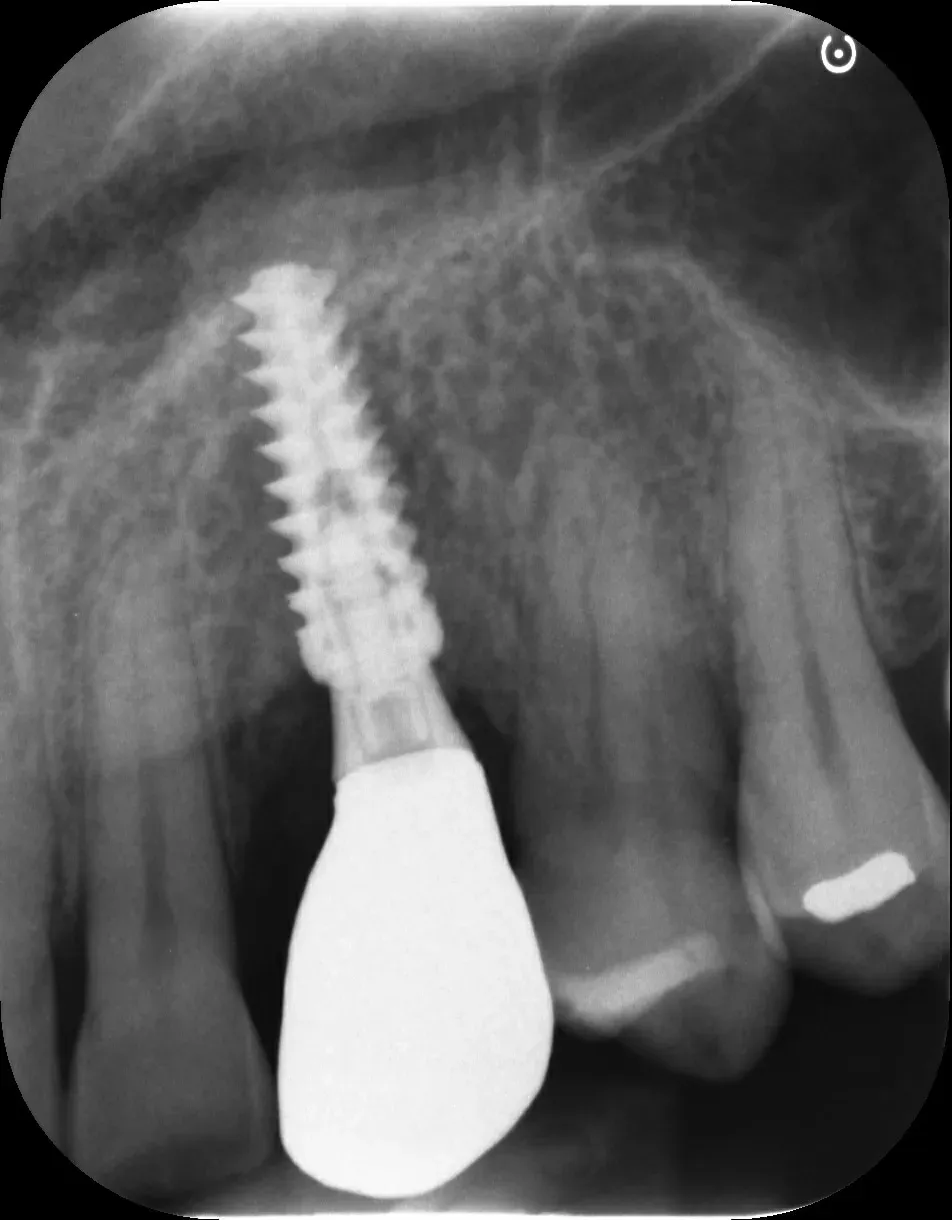

Per concludere il confronto tra le varie connessioni, l’immagine che segue è una radiografia con due impianti affiancati: un tissue-level ben posizionato fatto da un collega anni addietro e un impianto a connessione conica in posizione infracrestale con abutment della corretta lunghezza per il caso. Il secondo è un mio caso. È interessante notare come il cono dello spazio biologico sia identico. Se ben posizionati, tutti gli impianti funzionano egregiamente (l’impianto più vecchio inizia a soffrire un pochino, ma questa è un’altra storia).